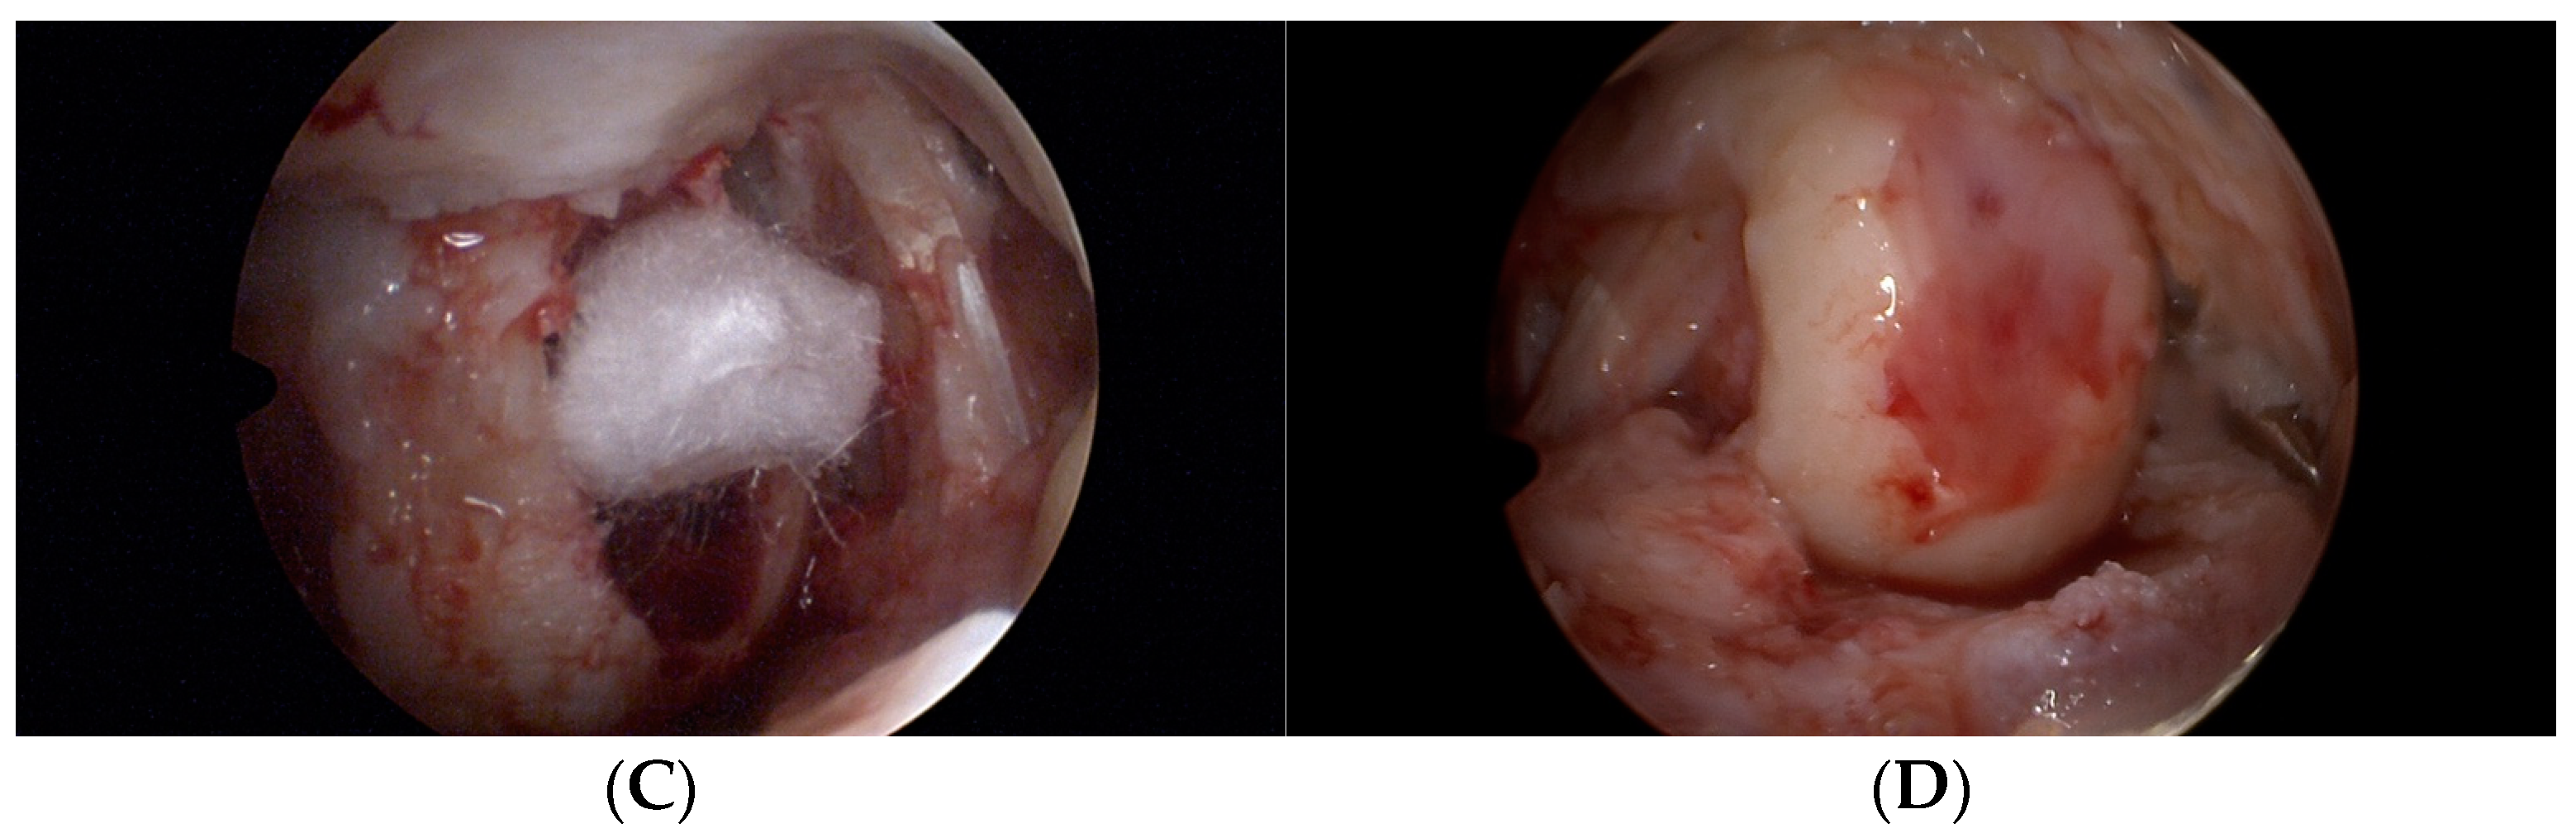

3.1. KOOS and SF-36 Scales